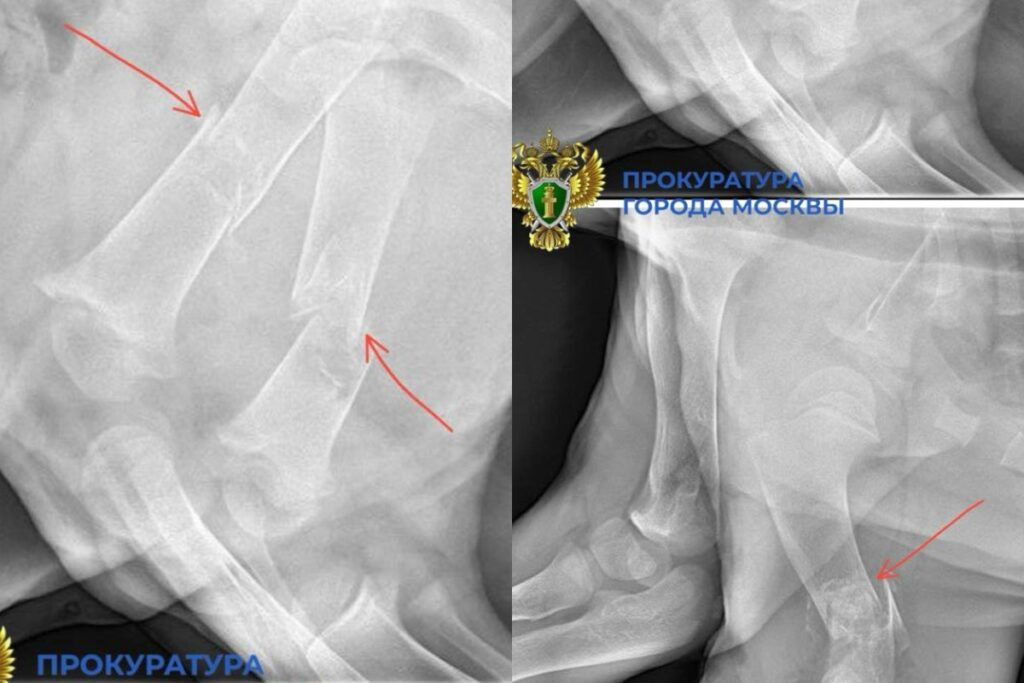

«При первичном ветеринарном осмотре у животного выявлены многочисленные травмы: переломы трех конечностей, повреждение позвоночника, а также общее истощение костной ткани, вероятно вызванное ненадлежащими условиями содержания и питания», — говорится в сообщении.